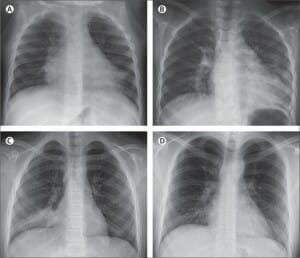

Pneumococcale pneumonie

Pneumococcale pneumonie is de meest voorkomende vorm va...

Lees Meer +